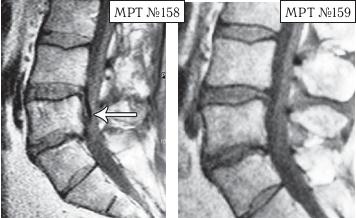

На МРТ № 150 в поясничном отделе позвоночника наблюдается рецидив грыжи после перенесённых пациентом двух хирургических операций: секвестрированная грыжа межпозвонкового диска в сегменте LV-SI . На МРТ № 151 наблюдается состояние поясничного отдела позвоночника после одного курса лечения методом вертеброревитологии. И ещё один пример устранения секвестрированной грыжи межпозвонкового диска.